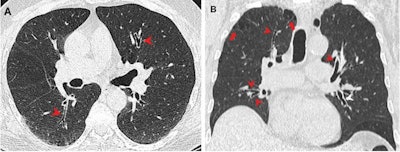

The study authors suggested that these findings may be linked to specific inhaling techniques while smoking marijuana. However, they called for larger, prospective studies to validate these results, noting that marijuana use is "bound to increase" with increasing legalization.

In an accompanying editorial, Dr. Jeffrey Galvin from the University of Maryland and Dr. Teri Franks from the Department of Defense Joint Pathology Center wrote that future studies "must" find a way to obtain a detailed history for how marijuana is inhaled, as well as the source, type, and strength of marijuana. They added that understanding the benefits and risks of marijuana smoking will need multiple disciplines to work together.

"Sophisticated imaging can provide both detailed microscopic anatomy and physiologic data that can form the basis of that understanding in the absence of lung tissue," they wrote.